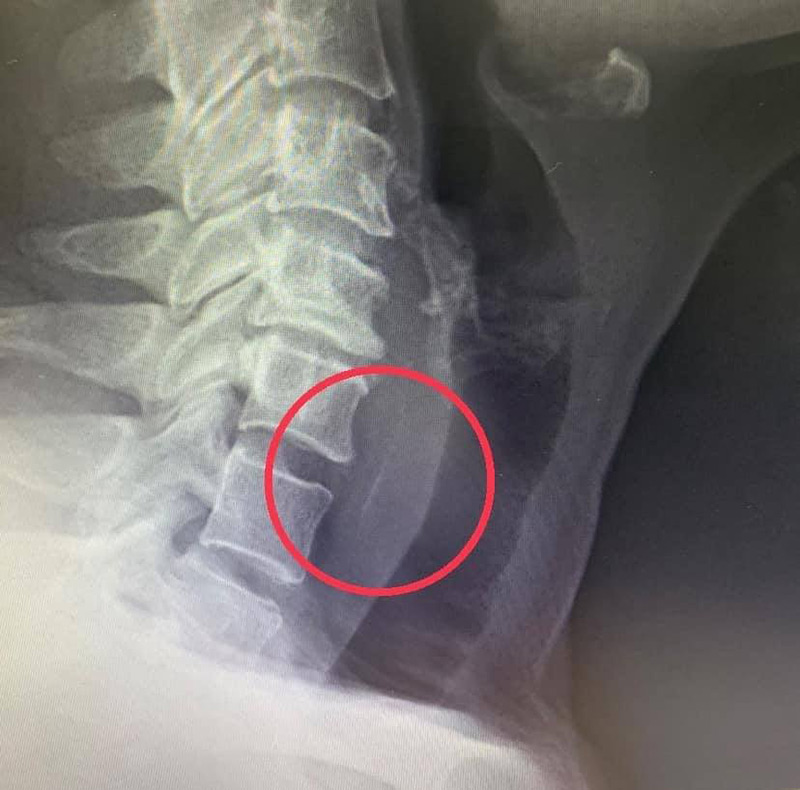

ผู้ป่วยเข้าห้องฉุกเฉิน พยาบาลซักประวัติ วัดสัญญานชีพ และประเมินความเจ็บปวดให้ระดับ 10 เต็ม 10 ถือเป็นความเจ็บปวดระดับสูงสุด จากนั้นแพทย์ส่องในลำคอไม่พบสิ่งแปลกปลอมใด ๆ จึงส่งเอกซเรย์ด่วนที่ลำคอและฉีดยาแก้ปวดให้ไปก่อน เมื่อดูจากที่เอกซเรย์แล้ว แพทย์พบว่ามีเงาทึบแสงสีขาว ๆ ขนาดประมาณ 2.5 เซนติเมตร ขวางอยู่ที่หลอดอาหารส่วนบน จึงรีบนำตัวผู้ป่วยกลับห้องฉุกเฉินเพื่อให้น้ำเกลือ และปรึกษาแพทย์ผู้เชี่ยวชาญด้าน หู คอ จมูก จากนั้นได้ส่งเข้าห้องผ่าตัดทันที